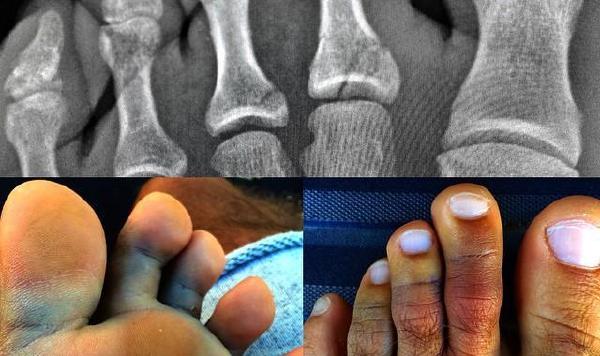

Con questa foto postata sul profilo instagram, Slater ha confermato ufficialmente la rottura di due dita del piede sinistro durante una session alle Fiji, dove si era rifugiato dopo il Rip Curl Pro in Portogallo.

Fortunatamente il medico fatta dal medico è di 3-4 settimane, dopodichè Slater potrà tornare in acqua e sarà quindi presente al Pipe Masters per cercare di vincere un dodicesimo titolo mondiale.